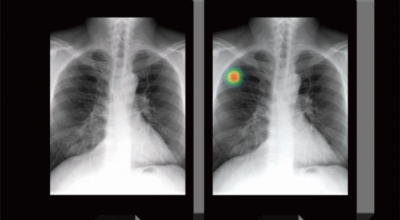

폐암 검사는 X-ray를 통해서 검사하는데 , 크기가 작거나 구석에 위치한 경우 확인이 어려운 경우도 있답니다. 그리고 조직 검사를 통해서 정확한 진단을 하게 되어요. 폐암이 발견되면 종양의 크기나 전이 여부 , 위치에 따라서 수술 여부를 결정하게 되어요.